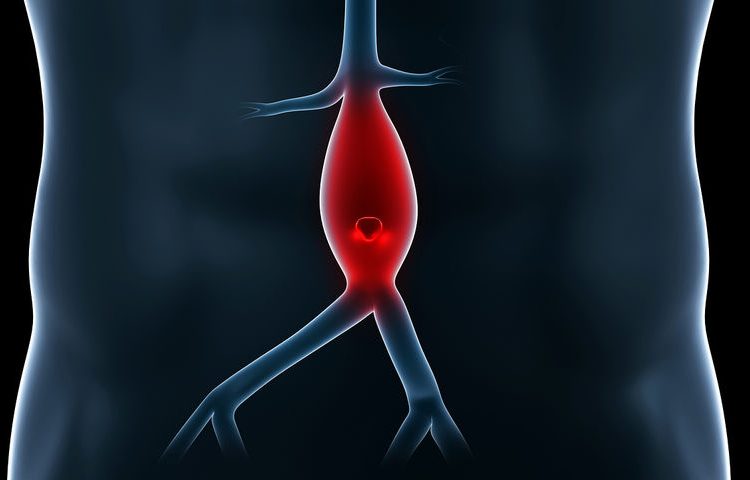

Ανεύρυσμα ονομάζεται η παθολογική αύξηση της διαμέτρου ενός αγγείου τουλάχιστον κατά 50%. Έτσι, για την κοιλιακή αορτή, όπου η φυσιολογική διάμετρος στους ενήλικες είναι περίπου 20 χιλιοστά, ως ανεύρυσμα θεωρείται κάθε διάταση πάνω από 30 χιλιοστά.

Το ανεύρυσμα κοιλιακής αορτής (ΑΚΑ) είναι μια σχετικά συχνή και δυνητικά απειλητική για την ζωή πάθηση. Η πλέον τρομακτική και θορυβώδης επιπλοκή του ΑΚΑ είναι η ρήξη, η οποία συχνά οδηγεί και στον θάνατο του ασθενούς. Ενώ και τα μικρά ανευρύσματα μπορεί να οδηγηθούν σε ρήξη, μεγαλύτερος είναι ο κίνδυνος για τα μεγαλύτερα και γι’ αυτόν τον λόγο η πρώιμη και έγκαιρη διάγνωση και η κατάλληλη εκτίμηση των πιθανοτήτων ρήξης αποτελούν τα κλειδιά για την διαχείριση των ΑΚΑ.

Η δημιουργία ενός ανευρύσματος κοιλιακής αορτής (ΑΚΑ) είναι στις περισσότερες περιπτώσεις μια εκφυλιστική διεργασία. Έρευνες έχουν δείξει ότι σε ασθενείς με ΑΚΑ υπάρχουν διαταραχές στην περιεκτικότητα του αρτηριακού τοιχώματος στις δομικές πρωτεΐνες ελαστίνη και κολλαγόνο. Δομικές και αιμοδυναμικές συνθήκες μοναδικές για την υπονεφρική αορτή μπορούν να εξηγήσουν την «προτίμηση» δημιουργίας ΑΚΑ σε αυτήν την ανατομική περιοχή, αλλά η στρατολόγηση των φλεγμονωδών κυττάρων στον έσω ελαστικό και τον έξω χιτώνα της αορτής φαίνεται να αποτελεί πρώιμο και καθοριστικό παθοφυσιολογικό γεγονός για την δημιουργία του ΑΚΑ.

Τα ανευρύσματα της κοιλιακής αορτής είναι συνήθως ασυμπτωματικά. Ένα αυξανόμενο σε διάμετρο ανεύρυσμα με πιθανότητα ρήξης ή ένα ραγέν ανεύρυσμα εμφανίζεται με αιφνίδιας έναρξης άλγος (συνεχές ή κωλικοειδές) στην οσφυική ή κοιλιακή χώρα που μπορεί να ακτινοβολεί στους γλουτούς, στις βουβώνες, στο όσχεο ή στους όρχεις, λιποθυμικό επεισόδιο και ταχεία κυκλοφορική κατάρριψη του ασθενούς. Οι συχνότερες επιπλοκές είναι η ρήξη (5-10/100.000 άτομα), τα θρομβοεμβολικά επεισόδια και η πίεση των παρακείμενων ιστών. Ο ρυθμός αύξησης του ανευρύσματος καθώς και η διάμετρός του αποτελούν βασικό κριτήριο για τον κίνδυνο ρήξης του ανευρύσματος. Συγκεκριμένα, υψηλής επικινδυνότητας θεωρούνται αυτά που έχουν διάμετρο μεγαλύτερη και μεγάλο ρυθμό αύξησης.